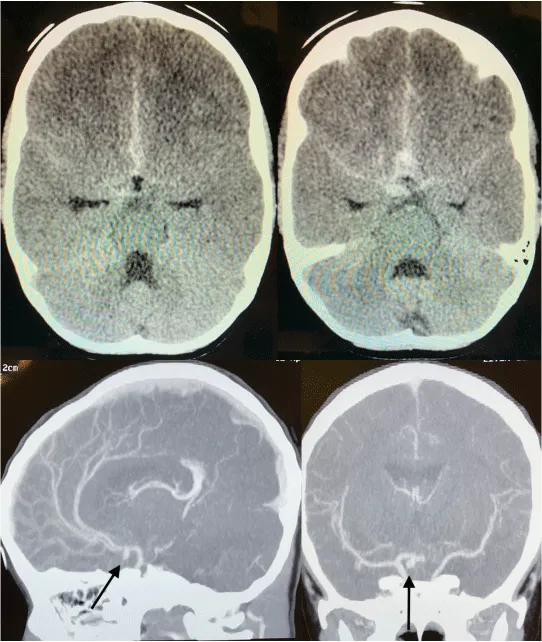

Romero FR, Vieira RB (2019) Intracranial aneurysm and subarachnoid hemorrhage in a 4-years-old patient. Glob J Rare Dis 4(1): 009-009. DOI: 10.17352/2640-7876.000014Pediatric intracranial aneurysm (PIA) is a rare condition, accounting 7% of all intracranial aneurysms. A slight male predominance is observed (two to one) and 25% of lesions are in posterior circulation. PIA should be considered in children with sudden headache and unexplained loss of consciousness. Treatment is challenging and technically demanding comparing with adult cases. Here we present a case of 4-years-old girl with sudden headache and seizures, with CT-scan showing subarachnoid hemorrhage and angio-CT with anterior communicating complex aneurysm. Our choice was microsurgical clipping and outcome was very good [1-5].